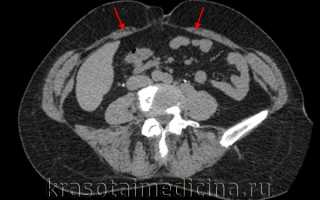

КТ ОБП. Расхождение прямых мышц живота (красные стрелки) у пожилой женщины.